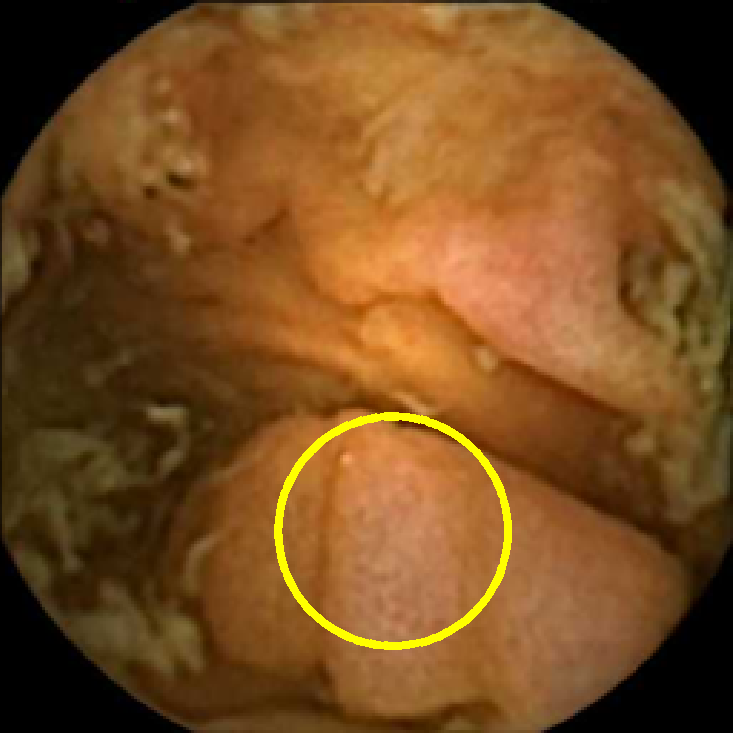

In Figure 5 we show the circles of radius corresponding to the features that were correctly classified as polyps by (29). We observe that the classifier was able to identify the polyps of a variety of shapes even in the presence of small amounts of trash liquid (first row) or when the polyps are located next to mucosal folds (rows two to four in column (c)).

The examples of incorrect classification of frames are presented in Figure 6. The first two examples show false negatives, each highlighting a possible source of classification error. The example in column (a) shows the case where the feature corresponding to the polyp was too stretched out and thus was rejected by the eccentricity criterion (21). In contrast, the feature corresponding to the polyp in column (b) has passed the combined geometric criterion (22), but the radius was below the threshold of the binary classifier. Examples in columns (c) and (d) show the two sources of possible false positives. The false positive detection in column (c) is due to insufficient illumination correction. The bright spot is not fully corrected at the pre-processing stage and subsequently generates a polyp-like feature in the mid-pass filtered frame that happens to pass through all the criteria. Finally, in column (d) a mucosal fold is classified as polyp. Note that such cases are the most difficult to deal with, as the mucosal folds can often be hard to distinguish from polyps even for a human operator.